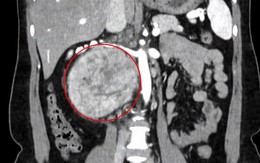

Sống khỏe - 10 phút trướcGĐXH - Khối u rất lớn, kích thước 12 cm nằm sau tĩnh mạch chủ, cạnh động mạch và hai tĩnh mạch thận, gây chèn ép... khiến người bệnh bị đau lưng âm ỉ.

Bệnh thường gặp - 1 giờ trướcGĐXH - Hình ảnh khối u tuyến thượng thận trái cấu trúc không đồng nhất, được xác định là nguyên nhân gây tăng huyết áp kéo dài.